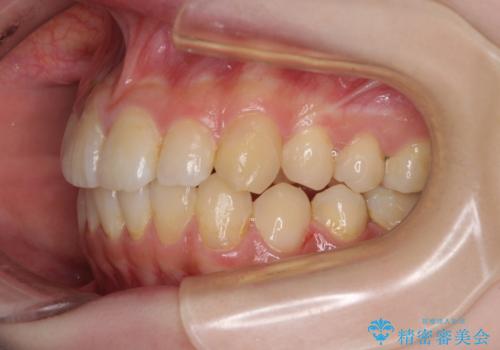

デコボコ歯列をきれいに インビザラインによる矯正治療

- 上下歯列全体のデコボコを気にして来院された患者様です。

主に下顎歯列全体の後方移動とIPR(歯と歯の間を削る)によってデコボコが解消するように設計し、インビザラインにより治療を行うこととしました。